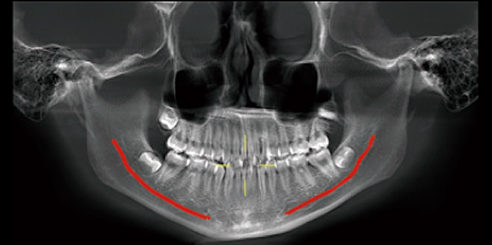

Furthermore, AI+PAN Dental CBCT Imaging enhances precision.

- The system rebuilds panoramic views directly from CBCT data using AI.

- Panoramic auto-focus and multi-layer technology select the best curve automatically.

- Therefore, the final image is cleaner and easier to read.